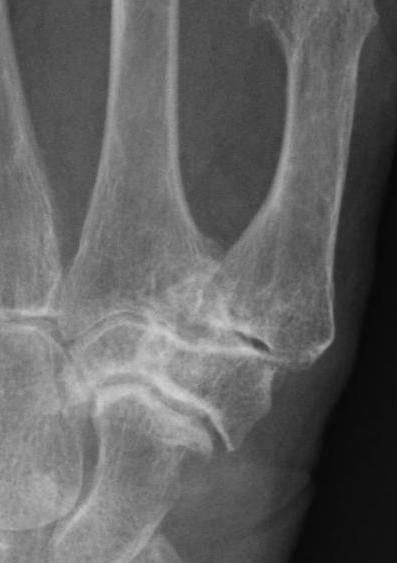

Eaton Classification

| Stage I | Stage II | Stage III | Stage IV |

|---|---|---|---|

|

Xray normal Synovitis |

Joint space narrowed Mild subluxation |

Severe joint space OA Radial subluxation of joint |

CMC + STT OA |

Clinical

![]()

Swan neck deformity

- Swan neck deformity - hyperextension of MCPJ secondary to dorsal subluxation of CMCJ